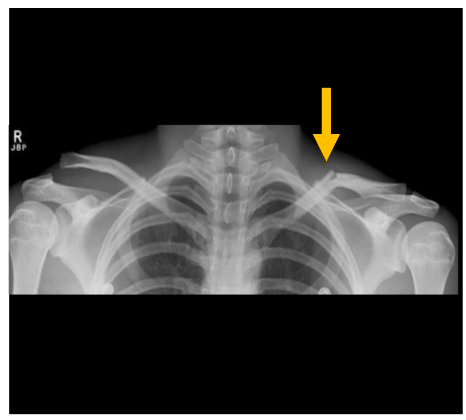

What is a clavicle fracture?

This is a fracture of the collar bone. This type of fracture is common in children.